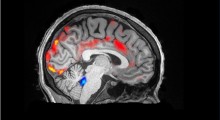

I ricercatori hanno allevato topi e nematodi con atassia telangiectasia (A-T) per lo studio. I pazienti di A-T hanno una degenerazione progressiva della parte del cervello responsabile del coordinamento, una riparazione carente del DNA, e altri sintomi caratteristici dell'invecchiamento precoce.

Lo studio indica inoltre che il danno al DNA può causare un funzionamento carente dei mitocondri, e che questo può portare ad un aumento della neurodegenerazione nei pazienti di A-T. L'aggiunta di sostanza NAD+ può fermare il danno ai mitocondri.

La comprensione dei meccanismi universali a livello cellulare è fondamentale per comprendere l'invecchiamento umano e il motivo per cui diventiamo più sensibili alle malattie quando invecchiamo. Speriamo che questa nuova conoscenza possa aiutare a rinviare i processi di invecchiamento fisico e a prevenire malattie come l'Alzheimer e il Parkinson.